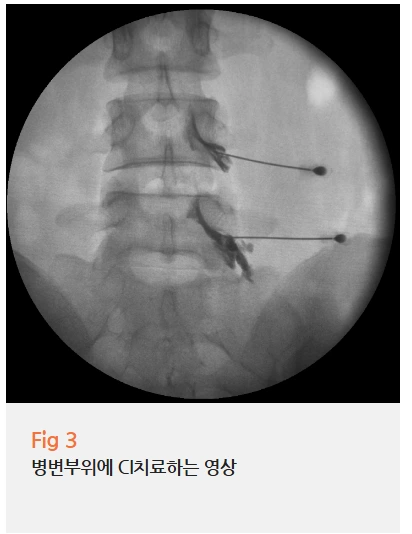

환자분께 소견을 설명드리고 CI(C-arm Intervention) 주사치료를 시행했어요.

병변 부위를 실시간으로 확인하며 주사를 놓는 방식이죠.